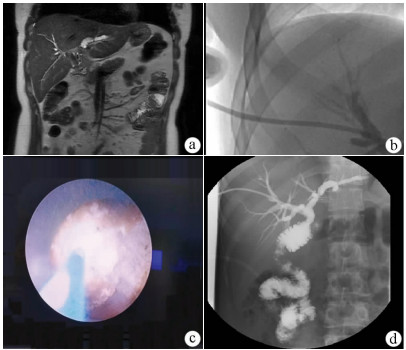

Effectiveness and safety of two-step percutaneous transhepatic choledochoscopic lithotomy in treatment of complex hepatolithiasis

Changhu DUAN, Xiaochen LIU, Jianfeng DUAN, Jianlong DING, Xirong ZHAO, Fan YANG, Lin WU, Lifei ZHAO, Sheng TAI

2021, 37(11): 2636-2641. DOI: 10.3969/j.issn.1001-5256.2021.11.029

Abstract(1219) HTML (808) PDF (1978KB)(100)

Abstract:

Objective  To investigate the clinical effect of two-step percutaneous transhepatic choledochoscopic lithotomy (PTCSL) in the treatment of complex hepatolithiasis.  Methods  A retrospective analysis was performed for the clinical data of 118 patients with complex hepatolithiasis who were admitted to 3201 Hospital of Xi'an Jiaotong University Health Science Center from January 2018 to June 2020, and according to the surgical procedure, they were divided into PTCSL group with 60 patients and surgery group with 58 patients. All patients were followed up for half a year to 3 years via telephone and outpatient service. The two groups were compared in terms of general information, perioperative indicators (including time of operation, intraoperative blood loss, incision length, time to first flatus and time to first defecation after surgery, time to extraction of abdominal drainage tube, and length of hospital stay), changes in liver function and inflammatory indicators, postoperative complications (bile leakage, acute cholangitis, wound infection, and venous thrombosis of lower extremities), stone clearance rate and recurrence rate, and quality of life. The two-independent-samples t-test was used for comparison of continuous data between two groups; the paired t-test was used for comparison between different periods of time within group; the chi-square test was used for comparison of categorical data between two groups.  Results  Compared with the surgery group, the PTCSL group had significantly shorter time of operation, time to first flatus and time to first defecation after surgery, and time to extraction of abdominal drainage tube, a significantly lower intraoperative blood loss, and a significantly shorter incision length (all P < 0.05). On day 1 after surgery, both groups had significant reductions in alanine aminotransferase (ALT) and aspartate aminotransferase (AST) (P < 0.05) and a significant increase in white blood cell count (WBC) (P < 0.05), and the PTCSL group had significantly lower levels of ALT, AST, and WBC than the surgery group (all P < 0.05). Compared with the surgery group, the PTCSL group had significantly lower incidence rates of postoperative bile leakage (5.0% vs 17.2%, P < 0.05), acute cholangitis (3.3% vs 13.8%, P < 0.05), wound infection (1.7% vs 10.3%, P < 0.05), and venous thrombosis of lower extremities (1.7% vs 12.1%, P < 0.05). Compared with the surgery group, the PTCSL group had a significantly higher stone clearance rate (58.3% vs 37.9%, P < 0.05) and a significantly lower long-term stone recurrence rate (10.0% vs 20.7%, P < 0.05). The PTCSL group had significantly higher quality of life scores than the surgery group (all P < 0.05).  Conclusion  For the treatment of complex hepatolithiasis, two-step PTCSL can effectively remove stones, with the advantages of fast postoperative recovery, low recurrence rate and incidence rate of complications, and high quality of life, and therefore, it is an effective alternative surgical procedure.